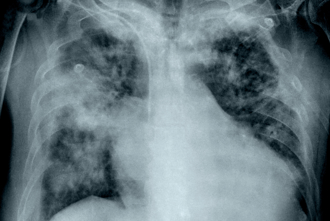

台湾中部地区时常因为台中火力发电厂,引发空气品质不佳的质疑。胸腔科医师苏一峰分享,有位30多岁的中部男子近日进行低剂量电脑断层LDCT健康检查,没想到肺部竟有10颗结节,其中更有一颗9mm的毛玻璃肺结节,但男子平时没有抽菸习惯、没有任何不舒服症状,贴文曝光后引发热议。

许多人觉得身体有异状时,可能会就医求助。胸腔科医师苏一峰分享,有位60岁女子因为长期咳嗽胸闷不舒服,到医院检查身体,没想到却发现胸腔「满天星肺结节」多达几十颗,原因是她从事制鞋工作,长期接触有机溶剂含甲苯等造成职业伤害,让苏一峰忍不住建议「更换工作比较安全」,贴文曝光后引发热议。

近些年来,肺癌有年轻化的趋势。对岸一名15岁的少年,因咳嗽就医,结果发现右肺毛玻璃状结节,手术后证实是肺癌,医生询问病史后发现,少年从小体弱多病,有肺癌家族史,家庭成员也有人抽菸,研判都是可能诱发他罹癌的因素。

健检发现肺部有疑似肺癌影像的毛玻璃肺结节时,很多人会陷入该追踪或手术切除的抉择。肿瘤科医师廖继鼎分享有位40岁女子,肺部有1颗2.2公分的毛玻璃结节,虽追踪3个月没变化,仍决定趁年轻及早手术拿掉,术后证明是早期肺癌,若换成是他,也会选择开刀,否则以他紧张型的个性,可能会食不下咽。

肺癌是国人最好发的癌症,且有年轻化的趋势。胸腔外科医师谢义山分享有一位年轻竹科工程师,没有吸菸,也没有肺癌家族史,单纯是因咳嗽好一阵子,因此自费做低剂量电脑断层检查,结果居然看到一颗1.3公分的毛玻璃结节,让他不寒而栗,「年轻人得肺癌好像不是那么罕见了。」

肺癌是国内最好发的癌症。急诊科医师魏智伟分享有位30岁女老师,在健检时发现有肺结节,她不在意,1年后因爬楼梯有点喘就医,竟发现已是肺腺癌末期,两侧肺叶、脑部都有肿瘤,提醒若有肺结节,尤其是直径超过0.5公分,或结节边缘不规则、雾雾的,都会提高恶性可能,应听医嘱严密追踪。

健检报告出现「肺部毛玻璃样病变」,常让人想到肺癌而陷入紧绷情绪。医师廖继鼎指出,出现毛玻璃影像并不等于一定罹癌,也不是末期警讯,判断危险性还须依病灶特徵、大小变化与个人风险因素和医师讨论,一开始先不用过度恐慌。

许多人工作时,可能会因为工作内容造成职业伤害。胸腔科医师苏一峰今(23)日分享,有位30多岁幼儿园老师没抽菸、不咳嗽,胸部却出现多达10颗肺结节,「大的肺结节居然到1公分以上!」,一问之下才知道,老师因为工作需要常常使用漂白水,进而导致生出肺结节,是化学性肺炎而非癌症,幸好治疗1年后顺利恢復健康,贴文曝光后引发热议。

肺癌是国人最好发的癌症,越来越多人自费做低剂量电脑断层检查,但报告中,常出现肺结节、毛玻璃结节,让民眾焦虑。对此,基因医师张家铭表示,最新研究发现,女性较好发毛玻璃结节,而毛玻璃结节一旦出现实质成分,肺癌风险可高达原本的13.77倍,就像是一颗埋在肺里的地雷,不能掉以轻心。